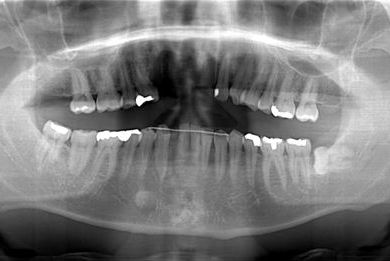

| 性別/年齢 | 男性 / 36歳 | ||||||||||||||||||||||||||||||||

| 主訴 | 事故で欠損した上部の歯4本、下1本のインプラント治療相談。 | ||||||||||||||||||||||||||||||||

| 治療内容 | インプラント2本(GBR、自家骨移植)、メタルボンドセラミック4本、結合組織移植術 | ||||||||||||||||||||||||||||||||